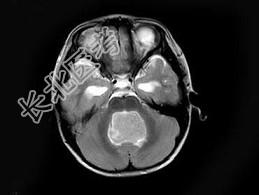

- 单项选择题女,3岁, 头痛4个月,MRI平扫及增强扫描, 最可能的诊断为 ( )

A、第四脑室脑膜瘤

B、第四脑室室管膜瘤

C、第四脑室乳头状瘤

D、第四脑室星形细胞瘤